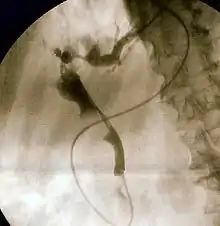

Fluoroscopic image of common bile duct